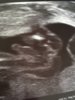

Voi kuinka ihania vauvoja. Harmi mamma-97 kun toi 4d kuva on jotenkin valottunut niin ei oo kovin selvä, mutta toisessa kuvassa näkyy ihanasti sivuprofiili <3

Joo ihan yllätti ensikertalaisen, kuinka selviä kuvia voi tulevasta lapsesta saadakin jo tässä vaiheessa. :) Ja voi miten ihania kuvia teillä muillakin on täällä. :love7